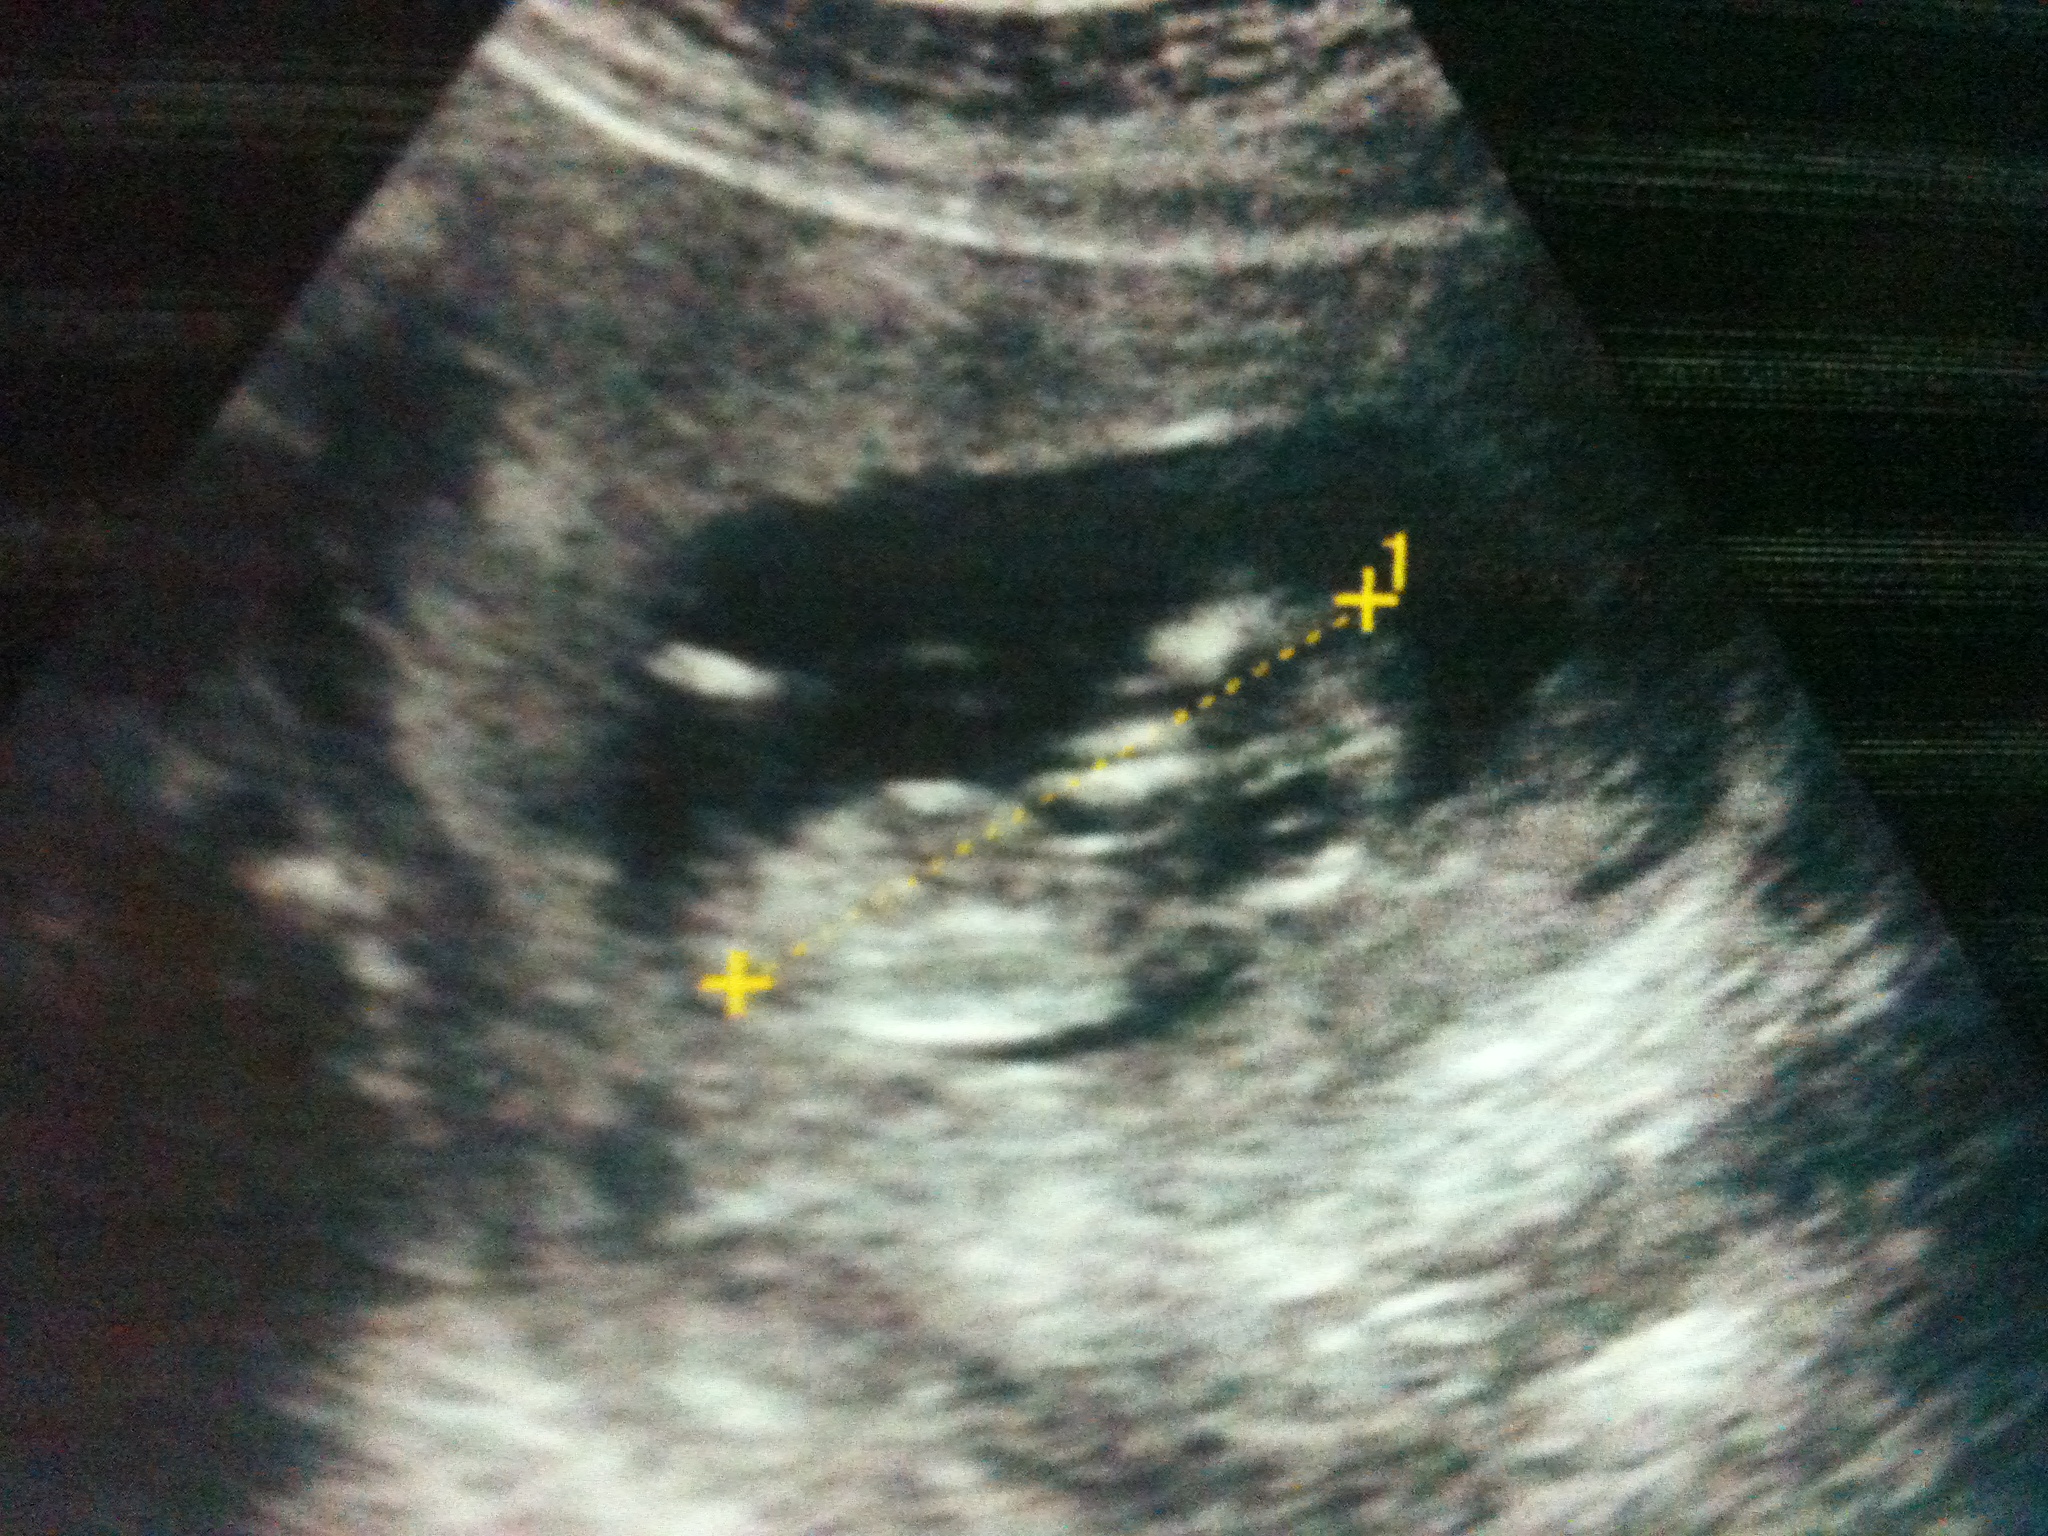

boy nub

Im 11 w 5 days in this one ! Thank u for ur responses ladies :))

looks to me like a boy nub. pointing up